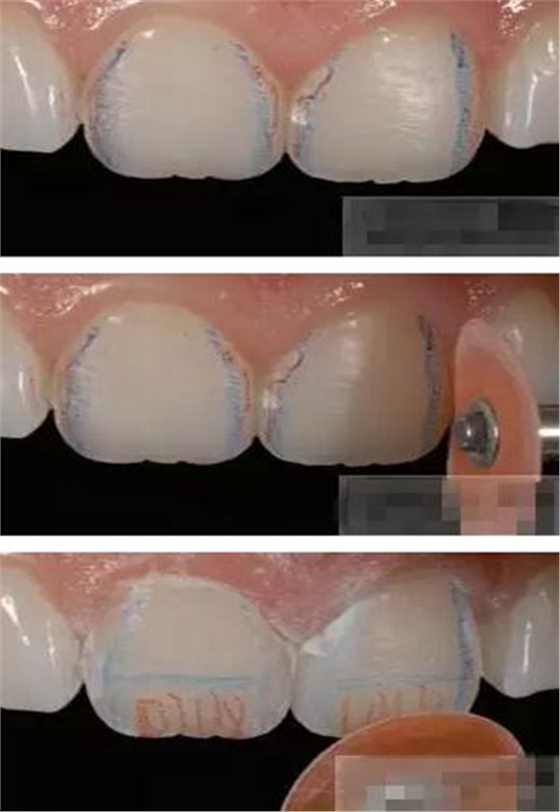

制作舌側(cè)背板

使用事先制作完成的硅橡膠模板。它是由技師在做好的美學(xué)蠟型的模型上制作的。這樣的方法為牙醫(yī)提供了許多便利:

a,美學(xué)蠟型可以使患者對(duì)可以達(dá)到的修復(fù)效果有直觀的了解,而且,患者也可以依據(jù)自己的美學(xué)素養(yǎng)對(duì)修復(fù)效果提出修改的意見(jiàn);

b,應(yīng)用硅膠模板牙醫(yī)可以觀察到牙體預(yù)備量;

c,硅膠模板使牙體修復(fù)簡(jiǎn)化,可以首先堆塑牙體的舌側(cè)面,這也是Dr.Vanini分層堆塑技術(shù)的基礎(chǔ),使用硅膠制作的膠刷會(huì)使堆塑更加簡(jiǎn)單;